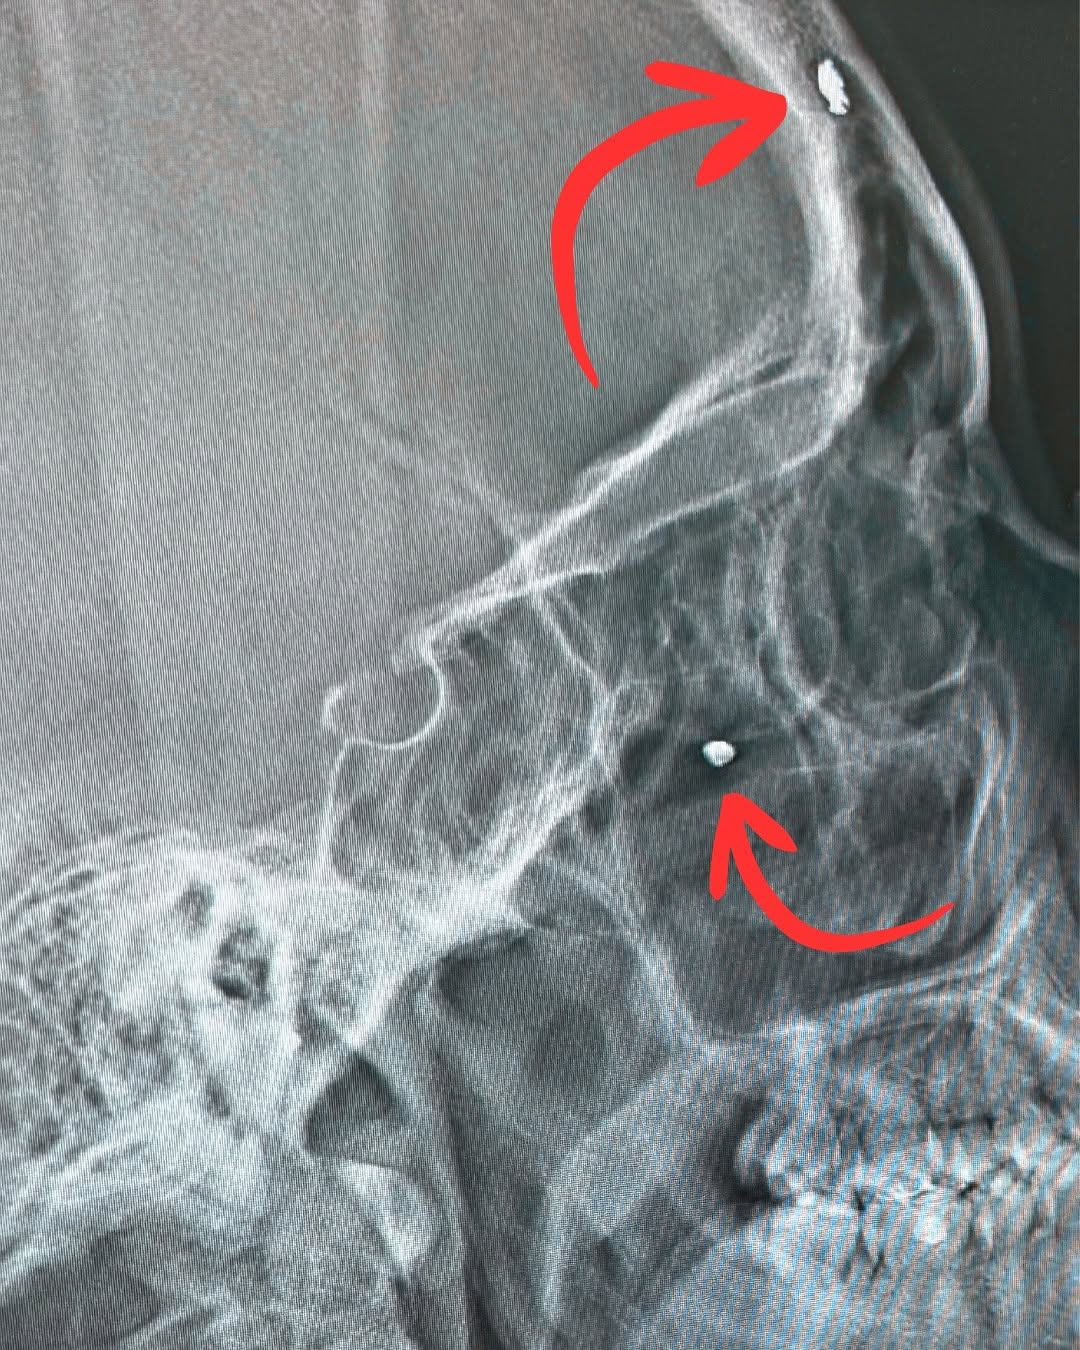

Yesterday’s X-ray lit up two tiny pieces of metal—one behind my eye, one in my forehead. Souvenirs from the day everything could’ve ended…and the reminder that it didn’t. I’m not posting this for shock value. I’m posting it because of the next photo. ➡️ This is why I’m still here: my people. Our messy, ordinary, perfect life. I’ve been through a lot over the years, and my default has always been: get up, keep moving, next thing. The downside? You can sprint past the miracle. You forget to sit with the fact that you made it through. That you’re still breathing. Still laughing. Still tucking your kids in. Today I’m pressing pause to feel it: grateful for the doctors, grateful for the prayers, grateful for the scar tissue and the second chances. Grateful for all of you. Grateful to simply be alive. Love you guys ❤️